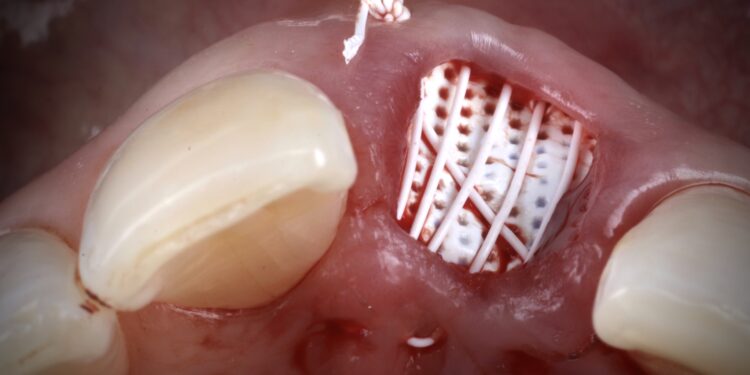

It was thus decided to carry out a ridge preservation graft to retain the existing alveolar ridge width and to use an open healing concept to encourage new soft tissue growth, increase keratinised tissue and avoid distortion of the mucogingival junction. This was carried out using the combination of MinerOss® Blend Allograft and a dense PTFE membrane.

This case demonstrates the power of ridge preservation whereby significant hard tissue grafting was avoided entirely in a patient with an extremely thin maxillary alveolus. The improvement in soft tissue contours is evident to be seen even with a healing period of 18 months post extraction with excellent keratinised tissue volume and no distortion in the mucogingival junction.